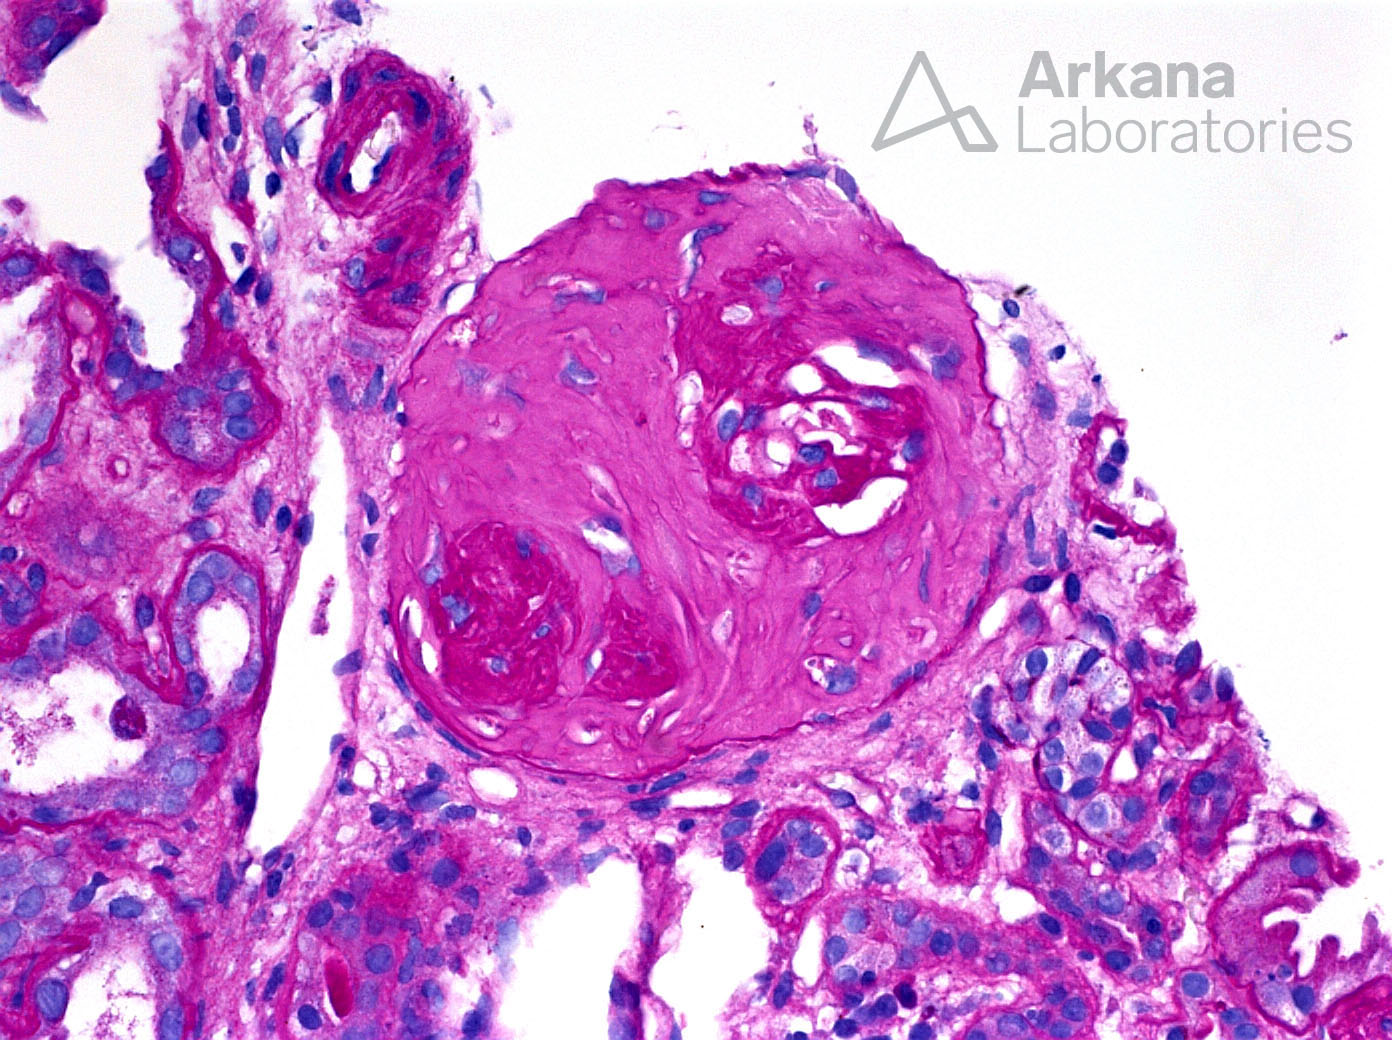

Fibrous Crescent